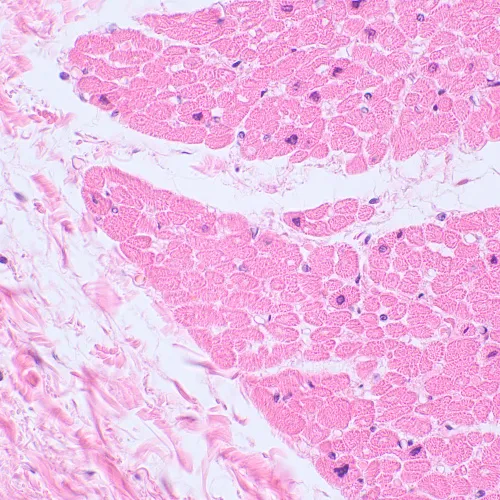

MAGUS Bio 230BL is a binocular microscope with achromatic objectives and LED illumination for observing biological samples such as smears and thin sections. The observations are made with the transmitted light microscopy technique (brightfield). The microscope can be equipped with optional darkfield, polarized light, and phase contrast devices. Areas of application: pharmaceuticals, medicine, biotechnology, veterinary medicine, forensics, agriculture, etc.